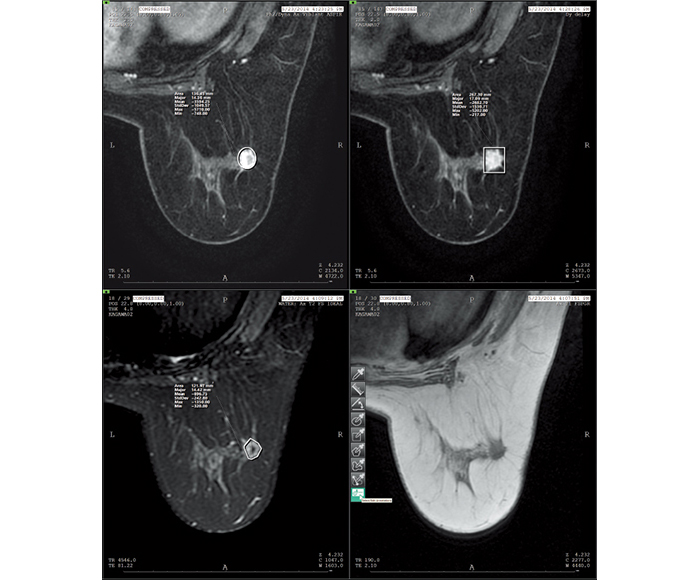

Various images, such as MG, BT, MR, CT, US, etc., are available for mammography diagnosis at the same time.

Values for ROI and X-ray gauging can be obtained from the information in each imaging modality.

ROI (Region of interest)